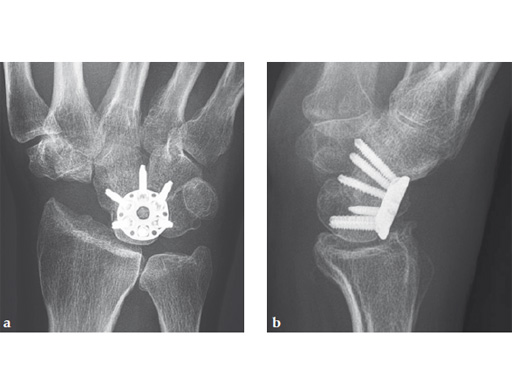

Fig 1ab Preoperative x-rays. Note the carpal collapse a a b nd DISI deformity.

Case 1: SNAC wrist stage 3. Operative procedure and technical details.

Case provided by Ladislav Nagy, Zrich, Switzerland, and Fiesky Nez, Valencia, Venezuela.

Fig 1ab Preoperative x-rays. Notice the midcarpal joint destruction and the DISI deformity of the lunate.